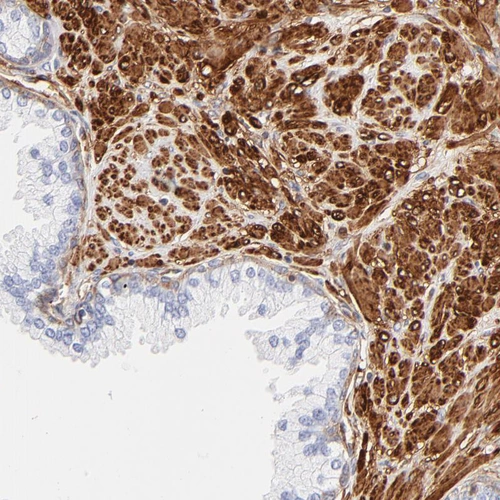

Immunohistochemistry analysis in human prostate and skeletal muscle tissues using HPA002925 antibody. Corresponding FLNA RNA-seq data are presented for the same tissues.